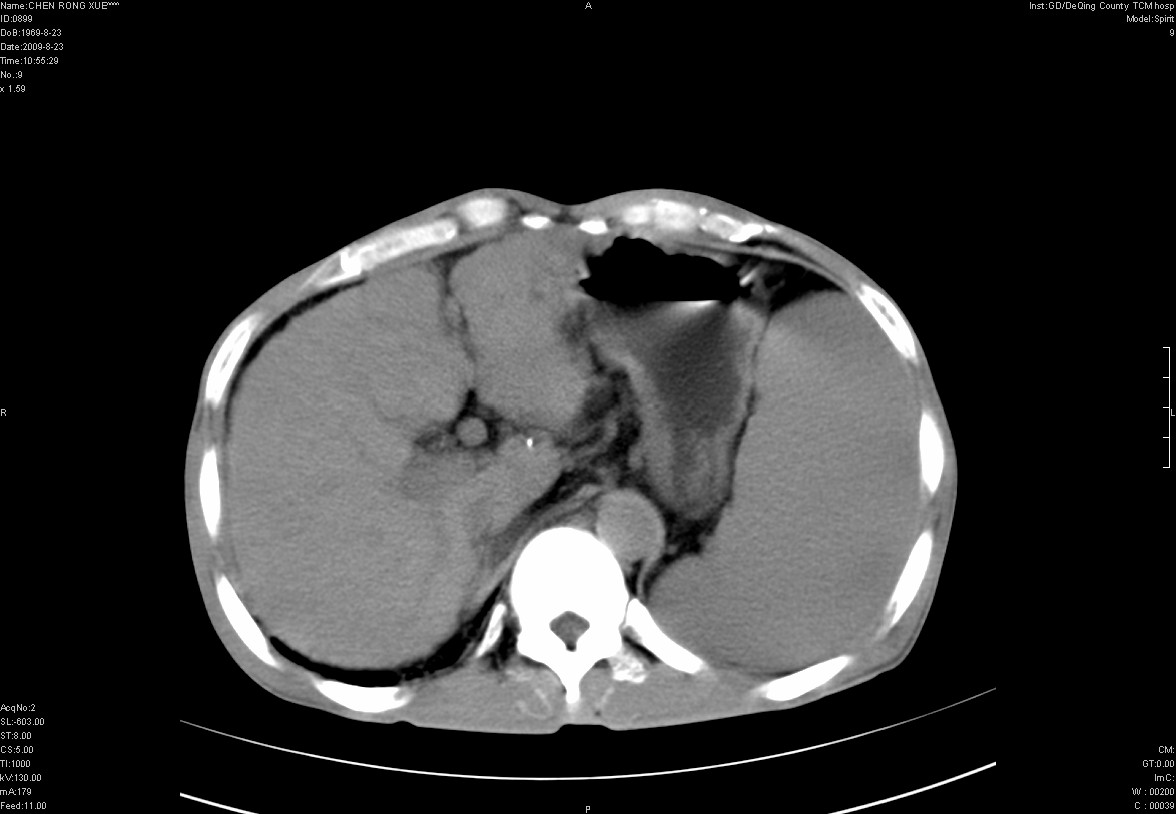

以下是引用zxl51642在2009-8-23 12:56:00的发言:[br]1、肝硬化、脾大;2、慢性胆囊炎;3、右肾占位并右侧腰大肌受侵,考虑恶性可能性大,建议增强扫描进一步检查。

以下是引用qiuleiyu在2009-8-23 15:17:00的发言:[br]1、慢性肝病,肝硬化,脾大,门脉高压。胆囊小结石。[br]2、右肾明显肿大,伴片状低密度灶,累及右侧腰大肌,肿瘤及炎症性病变皆有可能大,建议增强。

以下是引用zjzjr在2009-8-23 17:42:00的发言:[br]1、慢性肝病,肝硬化,脾大,门脉高压。胆囊小结石。[br]右肾脓肿波及肾周,建议增强

以下是引用dyqct在2009-8-23 16:53:00的发言:[br][quote]以下是引用qiuleiyu在2009-8-23 15:17:00的发言:[br]1、慢性肝病,肝硬化,脾大,门脉高压。胆囊小结石。[br]2、右肾明显肿大,伴片状低密度灶,累及右侧腰大肌,炎症性病变可能,建议增强。